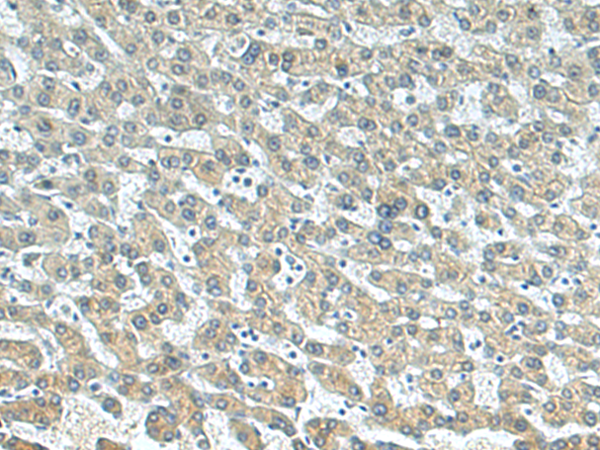

IHC positive control: |

Human liver cancer |

IHC Recommend dilution: |

100-200 |